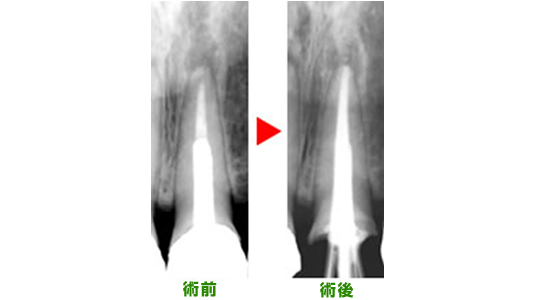

レントゲンを見てみると歯根の先までお薬が詰めてないため、本来お薬が詰まるはずのところに空間ができてしまい、細菌の繁殖が繰り返されてしまいます。

その結果、歯根の先には膿の袋ができて、炎症が骨の中で広がってしまいます。(写真上)

正確にお薬を詰め終わると、歯根の中で細菌の繁殖場所がなくなり、膿(うみ)の袋は徐々に消失します。